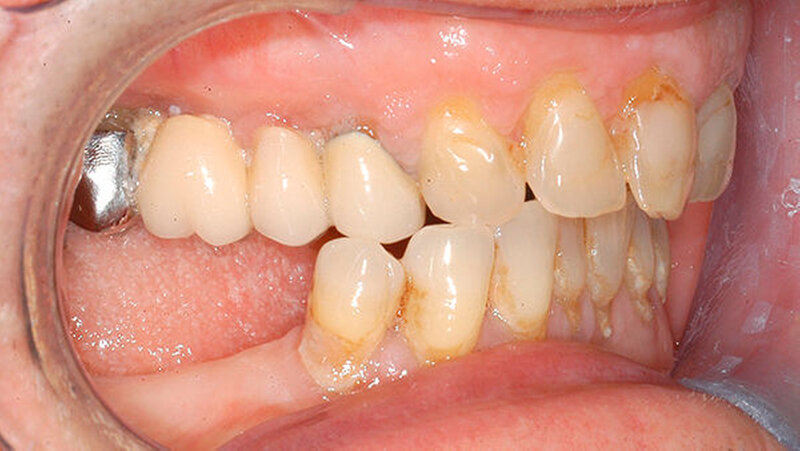

Bei der intraoralen Inspektion zeigte sich eine deutlich hyperplastische Gingiva mit Blutung auf Sondieren (BOP) (Abbildung 1). Da der Patientin die Handhabung einer Zahnbürste schwerfällt, zeigten sich auch deutliche Plaqueanlagerungen.

Aufgrund der schmerzhaften Gingivitis hatte die Patientin zudem Probleme mit der Nahrungsaufnahme. In der Panoramaschichtaufnahme (Abbildung 2) zeigt sich neben einem impaktierten Eckzahn ein Furkationsbefall der Molaren mit Konkrementen sowie ein altersentsprechender, generalisierter horizontaler Knochenabbau. Dennoch erschien uns das Volumen der Gingiva nach bereits erfolgter geschlossener Parodontaltherapie ungewöhnlich.